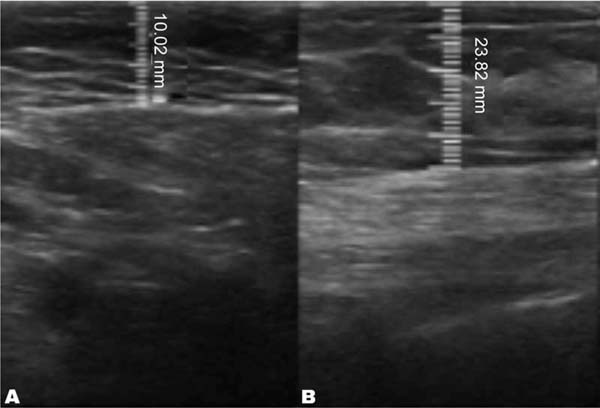

The measurement of subcutaneous tissue thickness is performed vertically, from the highest (right at the transition from the epidermis) to the lowest point (at the transition with the muscle tissue) of subcutaneous tissue thickness. This measurement is easily reproducible for those with basic ultrasound skills (►Fig. 2). In lipofilled breasts, the thickness of subcutaneous tissue was measured preoperatively and immediately after lipofilling, as well as at 15, 30, 90, and 180 days postoperatively. Measurements in millimeters were taken using ultrasound, including the vertical distance from the highest (closest to the epidermis) to the lowest point (closest to the adjacent musculature) of the subcutaneous tissue at the previously defined point. A GE LOGIQ P6 (GE HealthCare) ultrasound device with an 11L linear probe and a frequency range of 12 to 6 MHz was used, operated by a surgeon with postgraduate training in general ultrasonography (►Fig. 3).

In the decanted graft group, the average reduction compared with the initial thickness after lipofilling was 9.90% on day 15, 19.27% on month 1, 23.59% on month 3, and 26.36% on month 6. In the filtered graft group, the average reduction compared to the initial thickness after lipofilling was 7.74% on day 15, 14.85% on month 1, 20.67% on month 3, and 22.80% on month 6 (►Fig. 6). ►Figs 7–8 reveal the ultrasound change in subcutaneous tissue’s thickness before and after lipofilling. ►Figs. 9–10 show the pre-and postoperative results of one patient from each group.